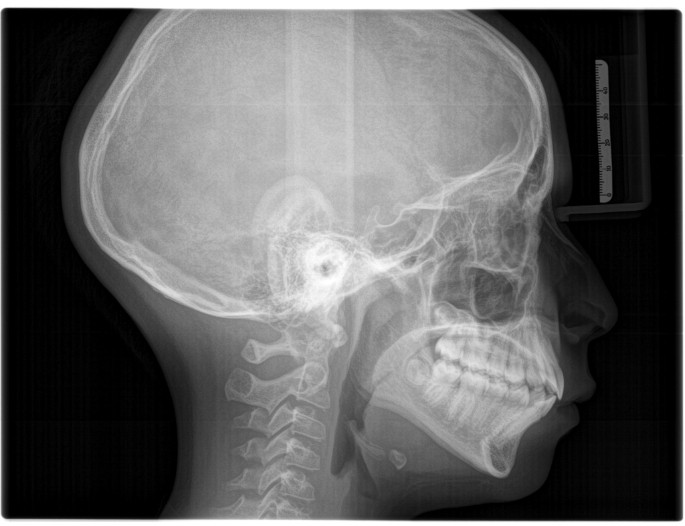

Permite medir y analizar las estructuras óseas del cráneo, cara y mandíbula (Ricketts, Jarabak, Roth, etc.). Esencial en ortodoncia y cirugía maxilofacial para definir planes de tratamiento.

Evalúa el perfil del paciente, sus tejidos blandos y óseos. Habitual en controles de ortodoncia, patologías craneales, cervicales y para cirugía ortognática o plástica.